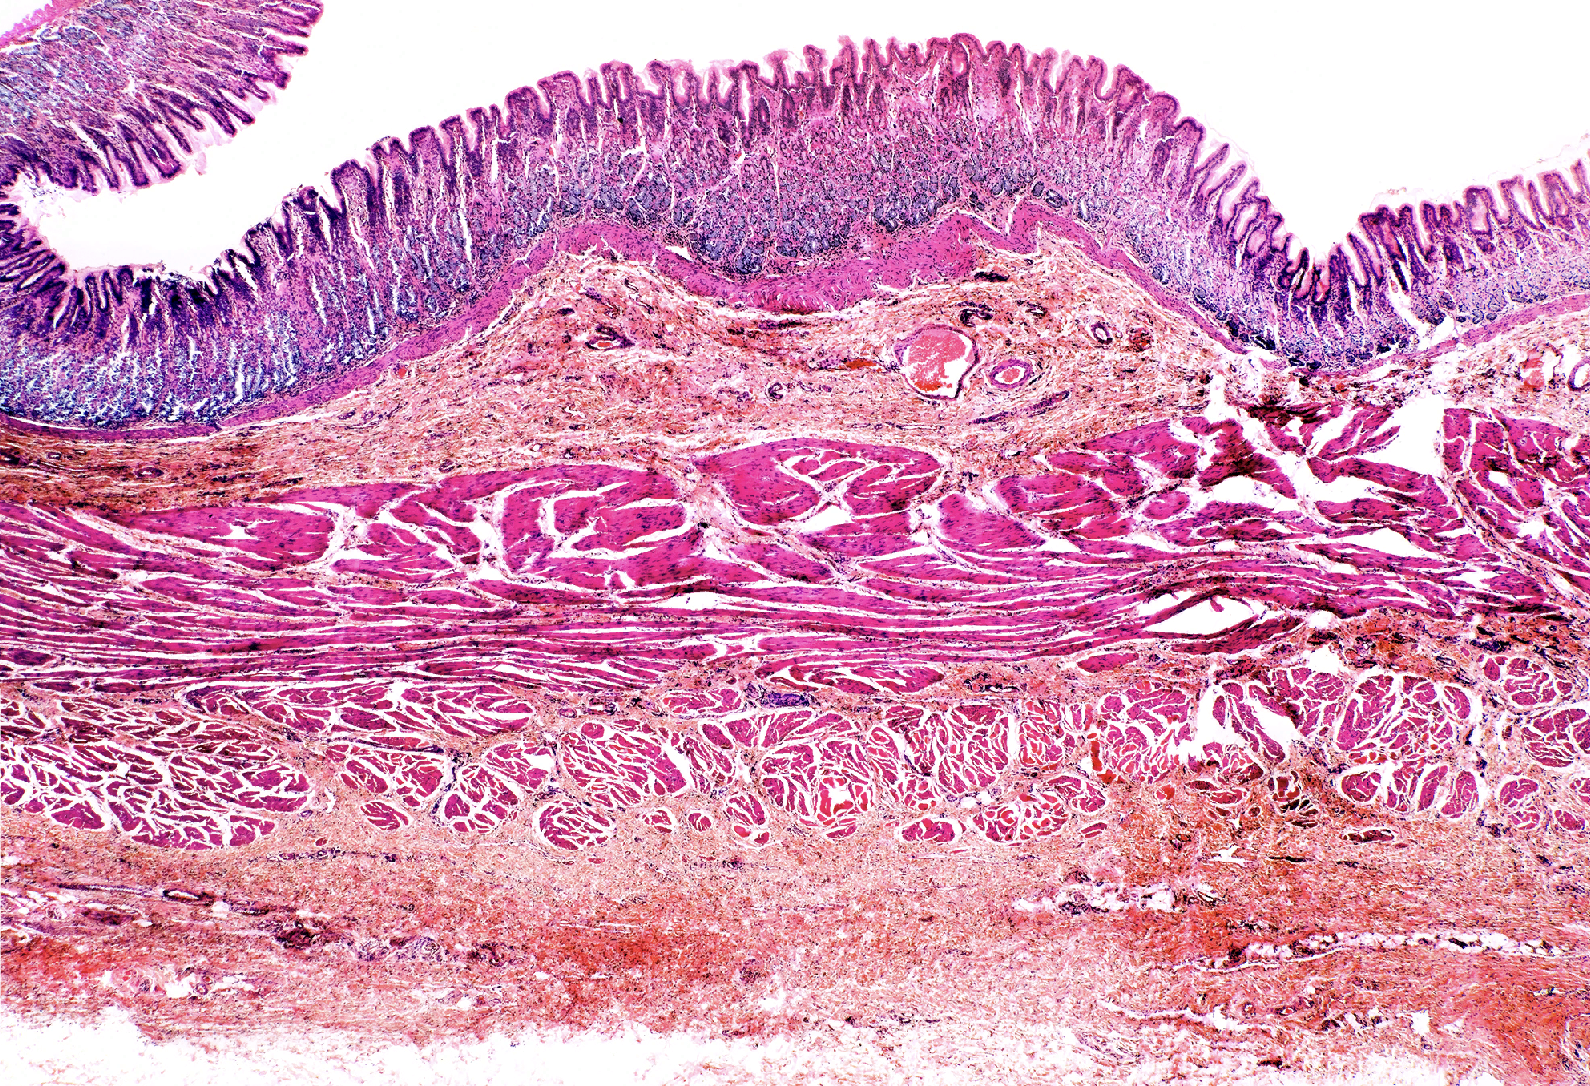

List the layers in the small intestine

Mucosa- ciliated pseudostratified columnar epithelium